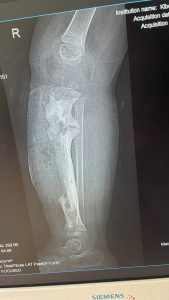

Das war die Ausgangssituation.